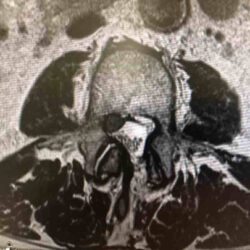

Cajas intersomáticas

¿Qué es una caja intersomatica?Una caja intersomática es un implante